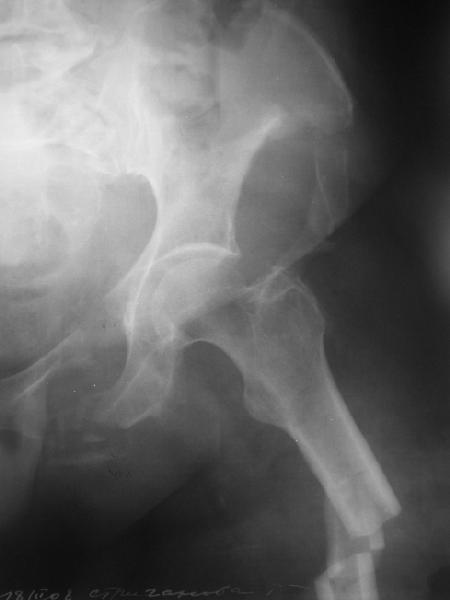

Здравствуйте уважаемые коллеги! Поступила пациентка, 61г, через 1 месяц после травмы, с двусторонним ротационно-нестабильным повреждением тазового кольца:

перелом боковых масс крестца с обеих сторон, переломы лонной и седалищной костей слева, отрывные переломы передних остей левой подвздошной кости, сегментарный перелом левой подвздошной кости. Кроме того у пациентки имеется сегментарный перелом левого бедра.

Перелом бедра не вызывает вопросов - планируем блокируемый остеосинтез стержнем, а вот при обсуждении тактики лечения переломов костей таза возник вопрос о необходимости синтеза остей подвздошной кости, учитывая сроки с момента травмы и наличие остеопороза могут возникнуть технические сложности. Если у кого-нибудь собственный опыт или ссылки на литературу об отдаленных результатах при не восстановлении сгибательного аппарата бедра?